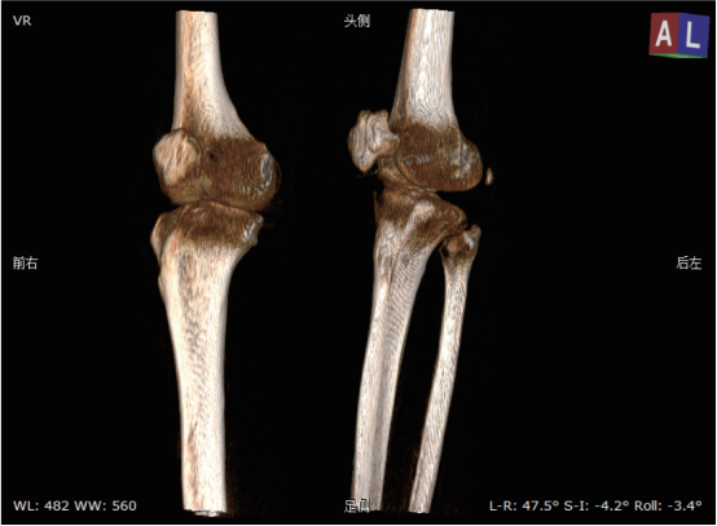

该系统核心优势在于整合动态透视与三维成像技术。在脊柱全长摄影、双下肢负重位检查中,可一次性获取颈椎至骶尾椎的高清全景影像,避免传统分段拍摄的拼接误差,为脊柱侧弯、关节畸形等疾病的力线测量和手术规划提供精准数据。其动态功能成像模块能实时捕捉关节运动状态下的解剖结构变化,清晰显示膝关节屈伸、肩关节活动时的软组织动态,显著提高韧带损伤、关节不稳等隐匿性病变的检出率。

医院将以该设备为依托,构建“影像检查-功能评估-治疗方案”一体化诊疗路径。如针对脊柱侧弯患者,可同步完成影像采集与三维力线分析,关节术后患者可通过动态成像评估康复进展,实现个性化治疗方案优化,进一步深化影像科与骨科、康复科、运动医学科的多学科协作。